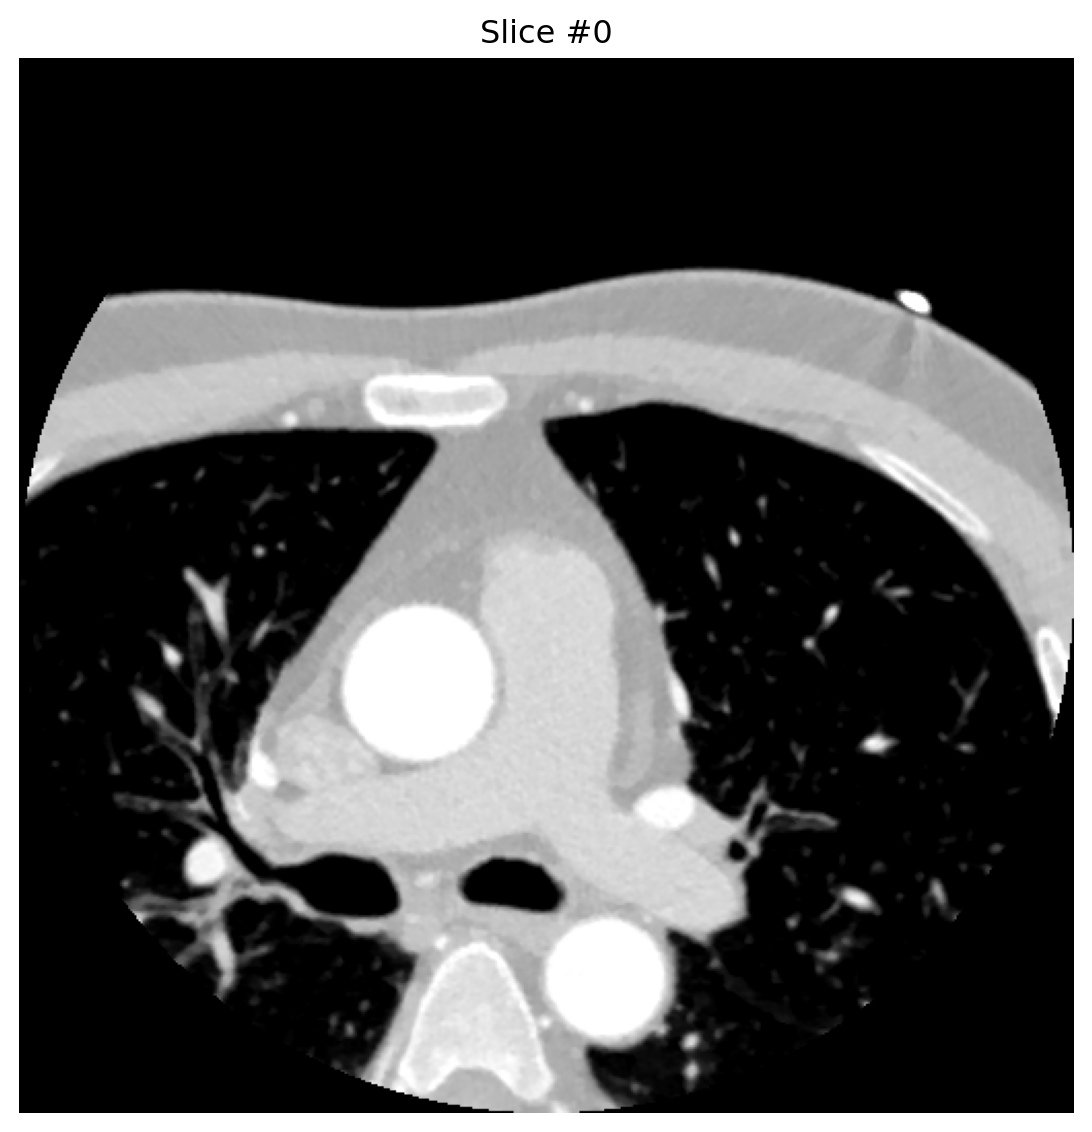

2.2. Processing + Visualization

def analyze_dicom_slice(slice_index):

buffer = BytesIO(dcb_stream.get_dicom_for_frame(slice_index))

dataset = pydicom.dcmread(buffer, force=True)

pixels = dataset.pixel_array.astype('float32')

if hasattr(dataset, 'RescaleIntercept'):

pixels += float(dataset.RescaleIntercept)

plt.figure(figsize=(8, 6))

plt.imshow(pixels, cmap='gray', vmin=-800, vmax=300)

plt.axis('off')

plt.title(f"Slice #{slice_index}")

plt.tight_layout()

plt.show()

return dataset

for idx in [0, 4, 8]:

analyze_dicom_slice(idx)

Conversion happens only when requested—no need to pre-expand entire series, saving space and latency.